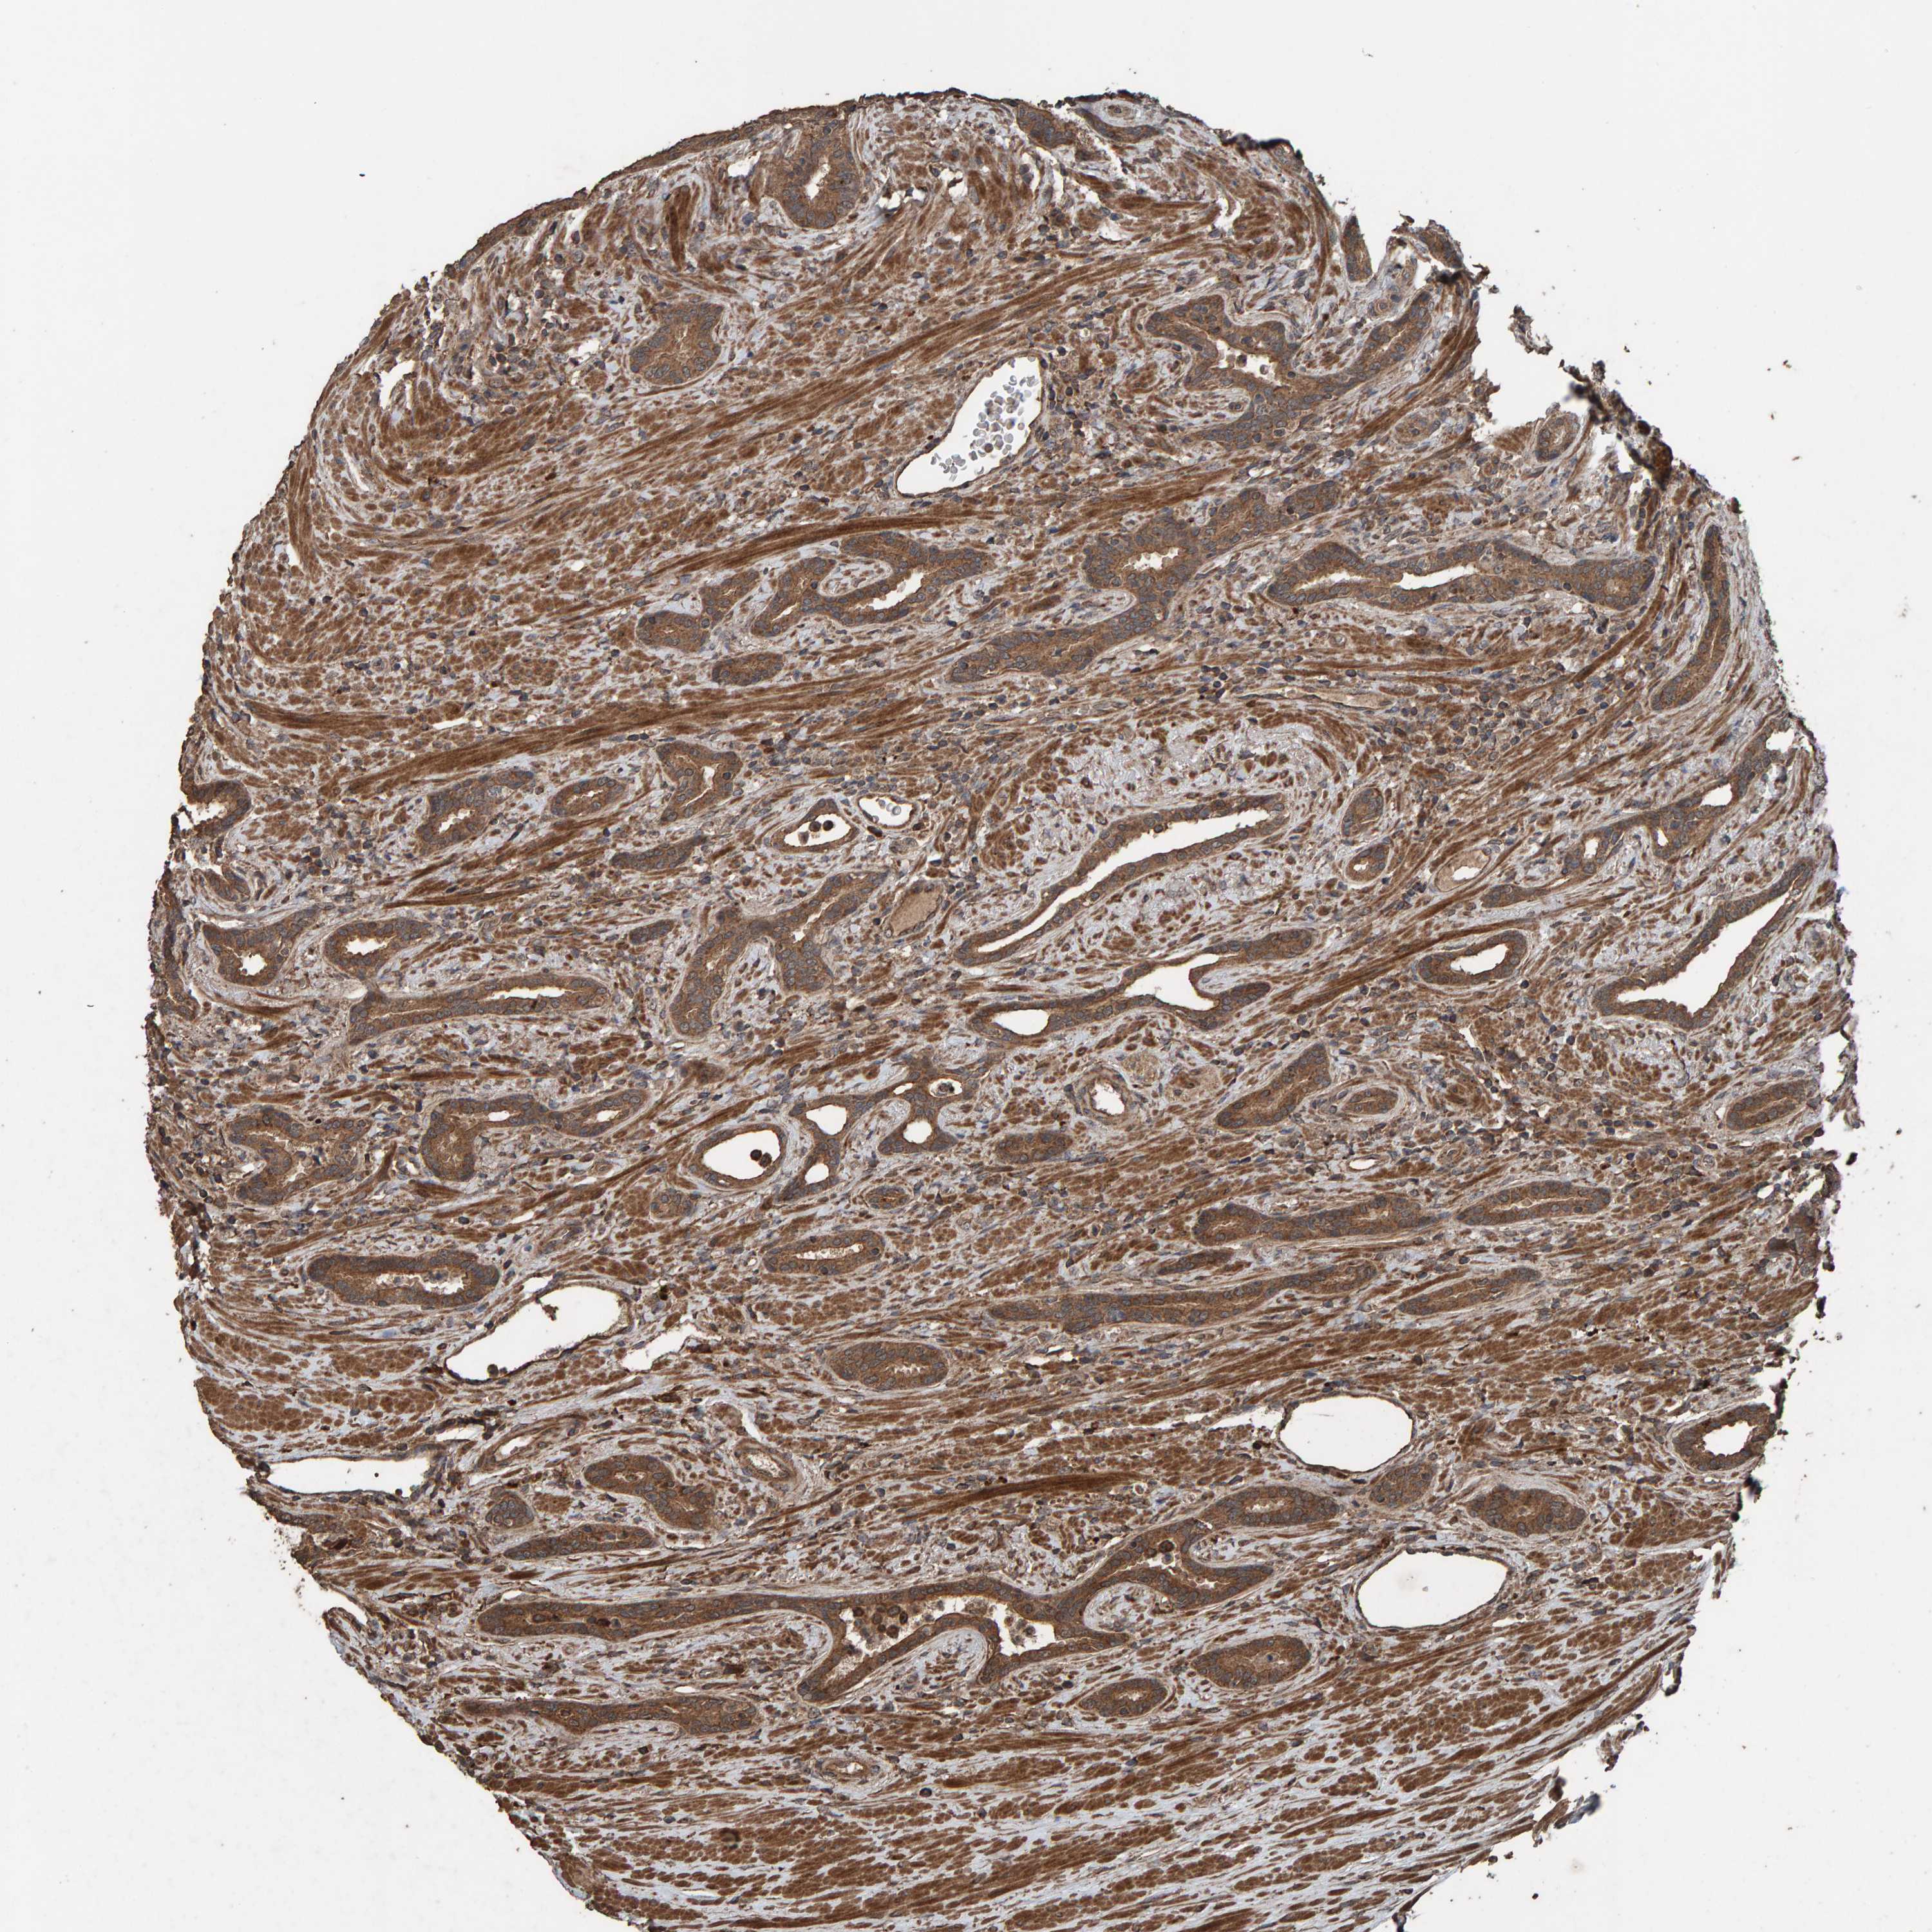

PROSTATE CANCER - Protein expressioni

A mouse-over function shows sample information and annotation data. Click on an image to view it in a full screen mode. Samples can be filtered based on level of antibody staining by selecting one or several of the following categories: high, medium, low and not detected. The assay and annotation is described here.

Note that samples used for immunohistochemistry by the Human Protein Atlas do not correspond to samples in the TCGA dataset.

Antibody stainingi

Antibody staining in the annotated cell types in the current human tissue is reported as not detected, low, medium, or high, based on conventional immunohistochemistry profiling in selected tissues. This score is based on the combination of the staining intensity and fraction of stained cells.

Each image is clickable and will lead to virtual microscopy that enables deeper exploration of all samples and also displays staining intensity scores, fraction scores and subcellular localization as well as patient and tissue information for each sample.

Antibody HPA023384

Staining

High

Medium

Low

Not detected

Intensity

Strong

Moderate

Weak

Negative

Quantity

>75%

75%-25%

<25%

None

Location

Nuclear

Cytoplasmic/membranous

Cytoplasmic/membranous,nuclear

Adenocarcinoma, High grade

Adenocarcinoma, Low grade